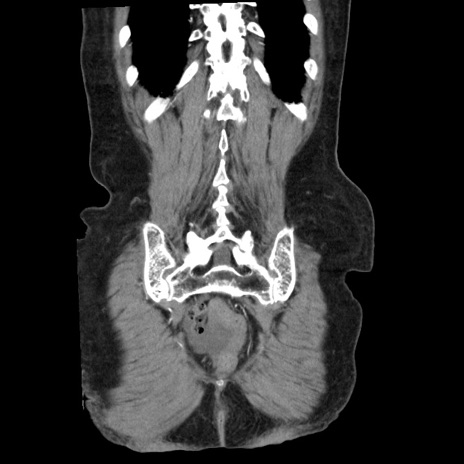

症例1(冠状断像)

【症例】80歳代女性

【主訴】腹痛

【現病歴】8時間前から腹痛あり来院。

【既往歴】糖尿病、脂質異常症、子宮体癌にて子宮全摘術

【身体所見】意識清明・会話良好だが腹痛で苦悶様、全腹部にわたって反跳痛と圧痛あり

【データ】WBC 13600、CRP 0.14、LDH 224、CK 90